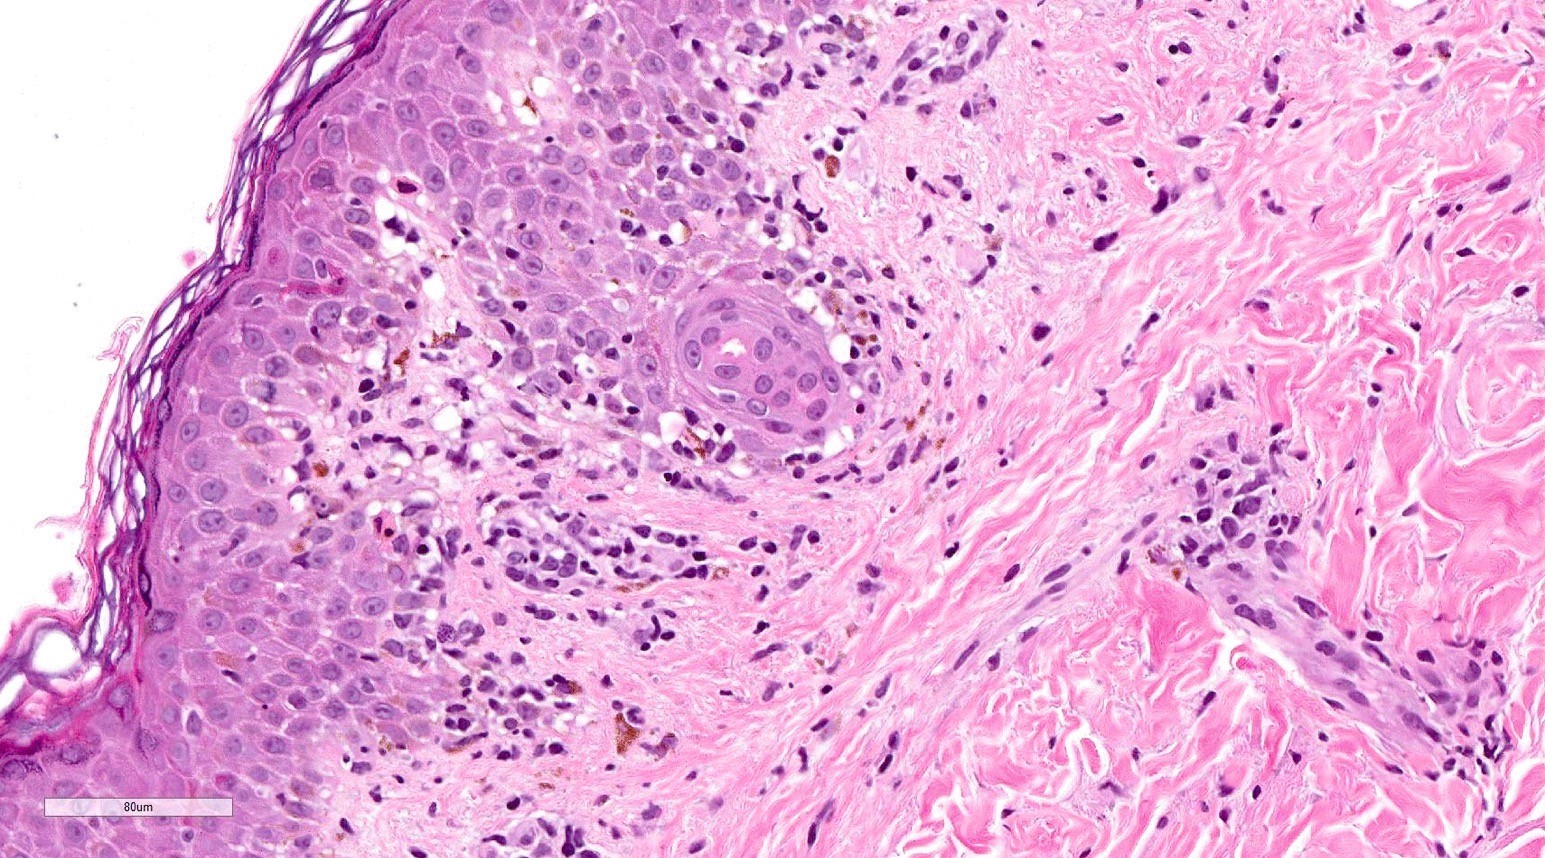

Microscopic (histologic) description

- Acute GVHD (Patterson: Weedon's Skin Pathology, 4th Edition, 2015)

- Mild to moderate superficial perivascular lymphocytic infiltrate with exocytosis of inflammatory cells into the epidermis and basal vacuolation, interface dermatitis

- Scattered, shrunken, eosinophilic keratinocytes with pyknotic nuclei, at all levels of the epidermis; often accompanied by 2 or more lymphocytes, producing the satellite cell necrosis - lymphocyte associated apoptosis

- Occasionally, rare eosinophils can be present; melanin incontinence is prominent in patients with darker skin types

- If severe, subepidermal microvesicles, subepidermal blisters and epidermal necrosis

- Lymphocytic infiltrate in GVHD after solid organ transplantation is usually brisk in comparison to the sparser inflammation following bone marrow transplantation

Microscopic (histologic) images

Contributed by Silvija P. Gottesman, M.D. and Ohoud Aljarbou, M.D.